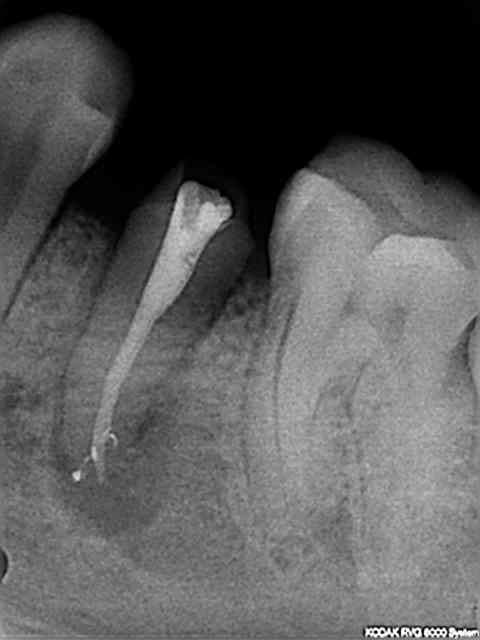

Voici un cas réalisé ce matin.

Reprise sur une 35 couronnée en Mai dernier dans un centre de soins.....

Commentaires des radios envoyées dans le message précédent : En 15 minutes, instrument 25 pour désobturer, préparer et prendre la longueur de travail. Instrument Niti 25 Endo Express pour la conicité.

Instrument 30, puis 35 et enfin le dernier instrument conicité 8%.

Obturation thermomécanique à 35/100 avec le ciment EZ-Fill (epoxy) remarquez les canaux latéraux et la densité de l'obturation.